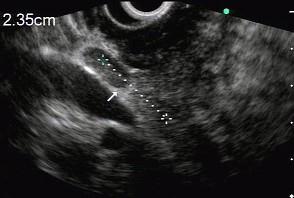

问题 男性,50岁,上腹隐痛,食欲不振3个月。1个月来出现黄疸且进行性加深,体重明显减轻,查体全身明显黄染,肝未触及,深吸气时可触到肿大胆囊底部,无触痛。化验血胆红素15mg/dl,尿检胆红素阳性图中胰腺病变可能的诊断是 ( )

选项 A.正常 B.胰腺囊肿 C.慢性胰腺炎 D.胰腺囊腺癌 E.胰腺癌

答案 E